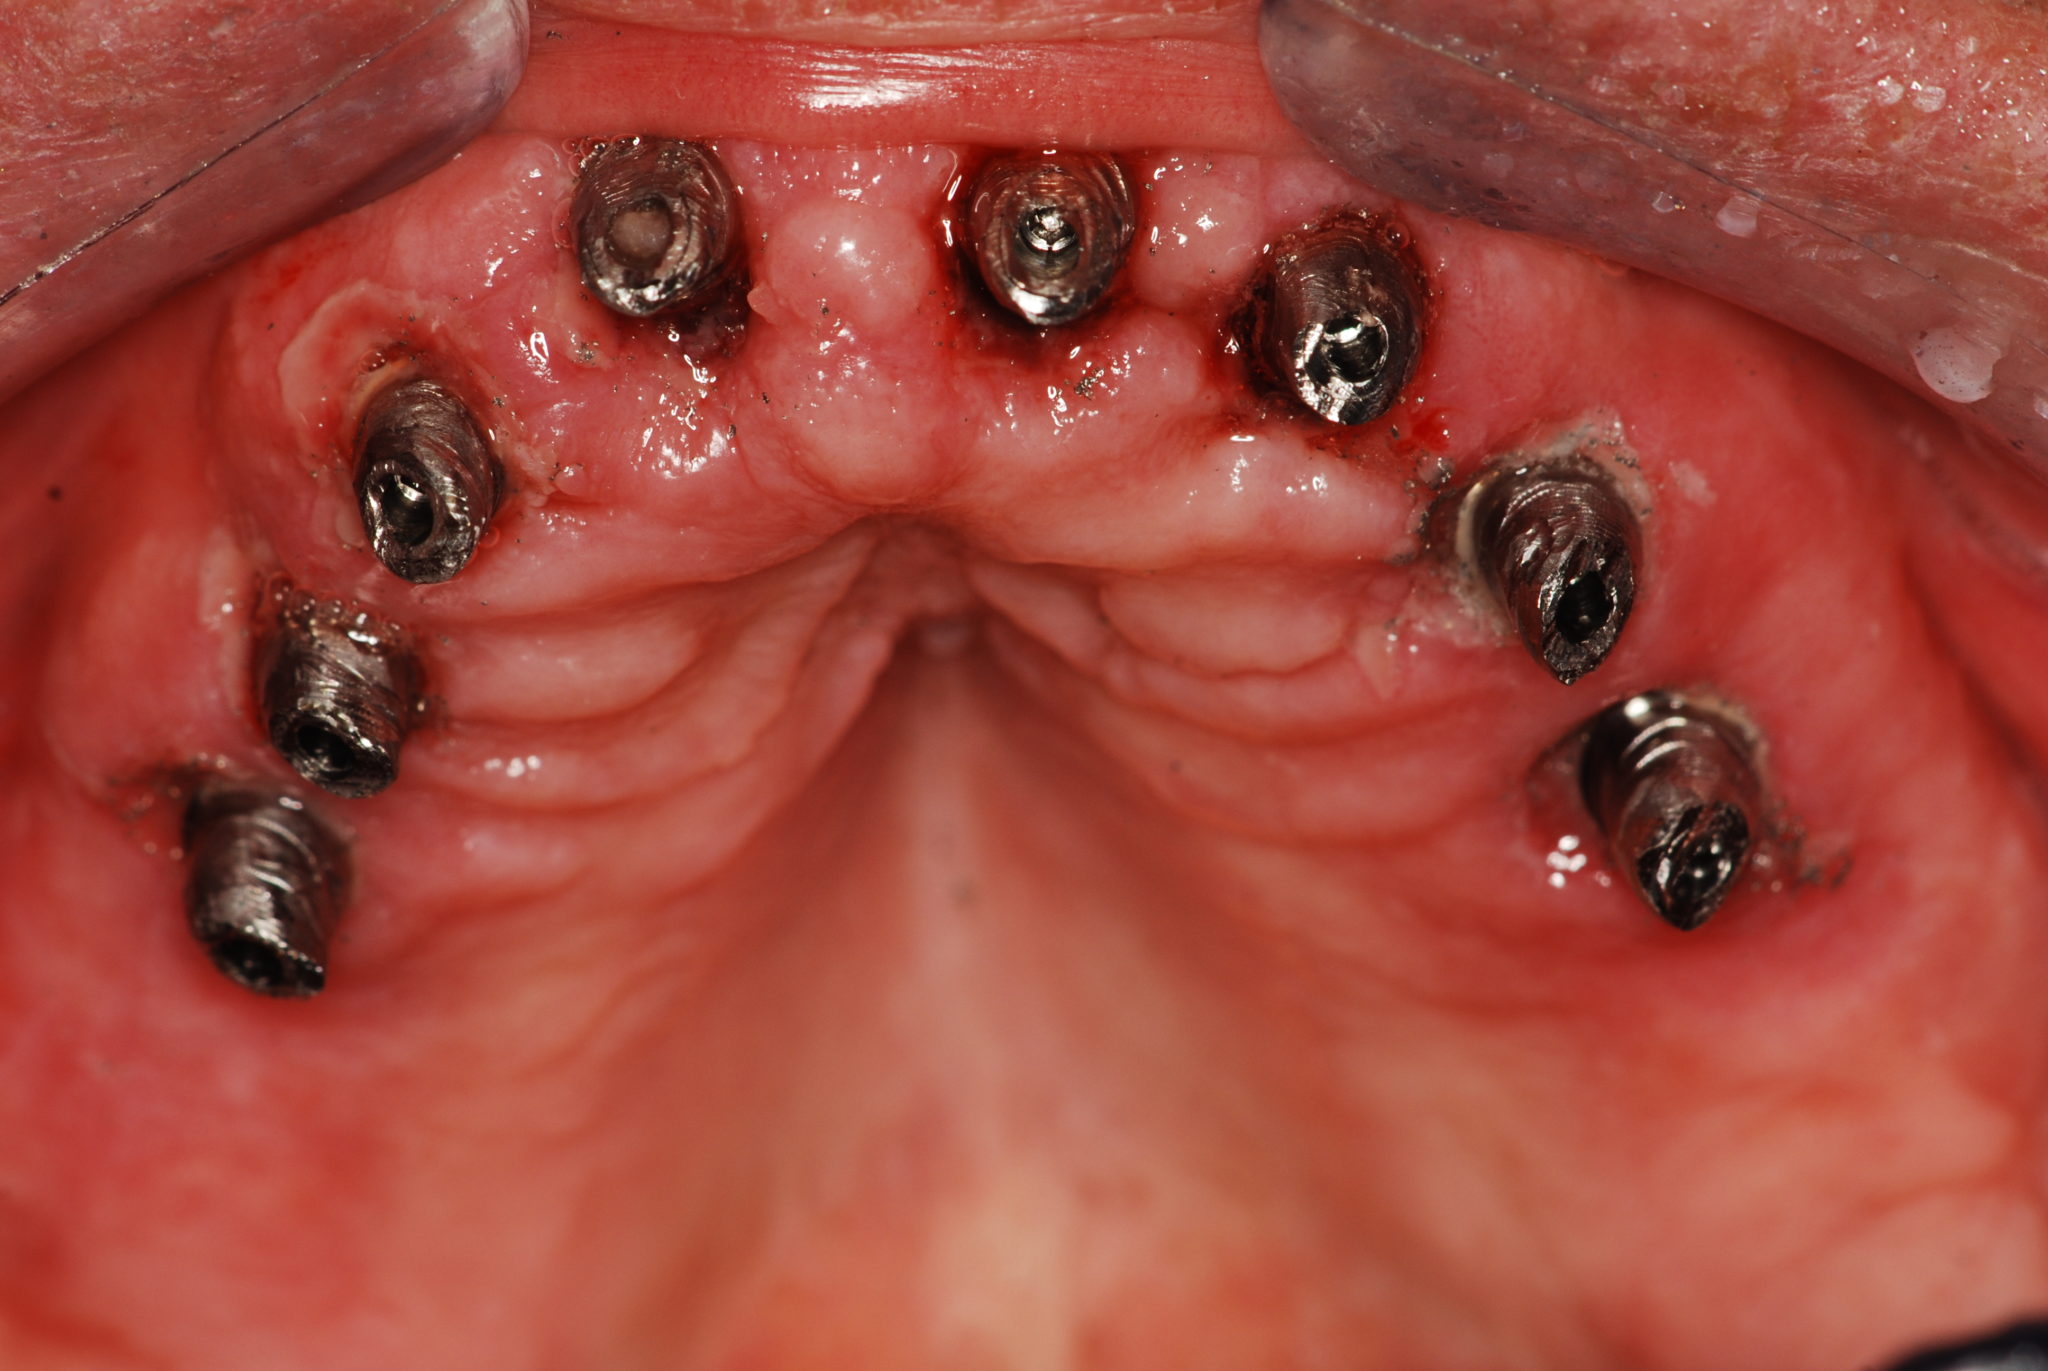

Casi Clinici: corone su impianti in titanio

Un impianto in titanio è costituito da 2 parti: una parte filettata detta fixture che va inserita nell’osso ed un’altra parte detta moncone o abutment che è il pilastro su cui verrà fissata la capsula che puo essre cementata o avvitata

CASO 9 (2024)